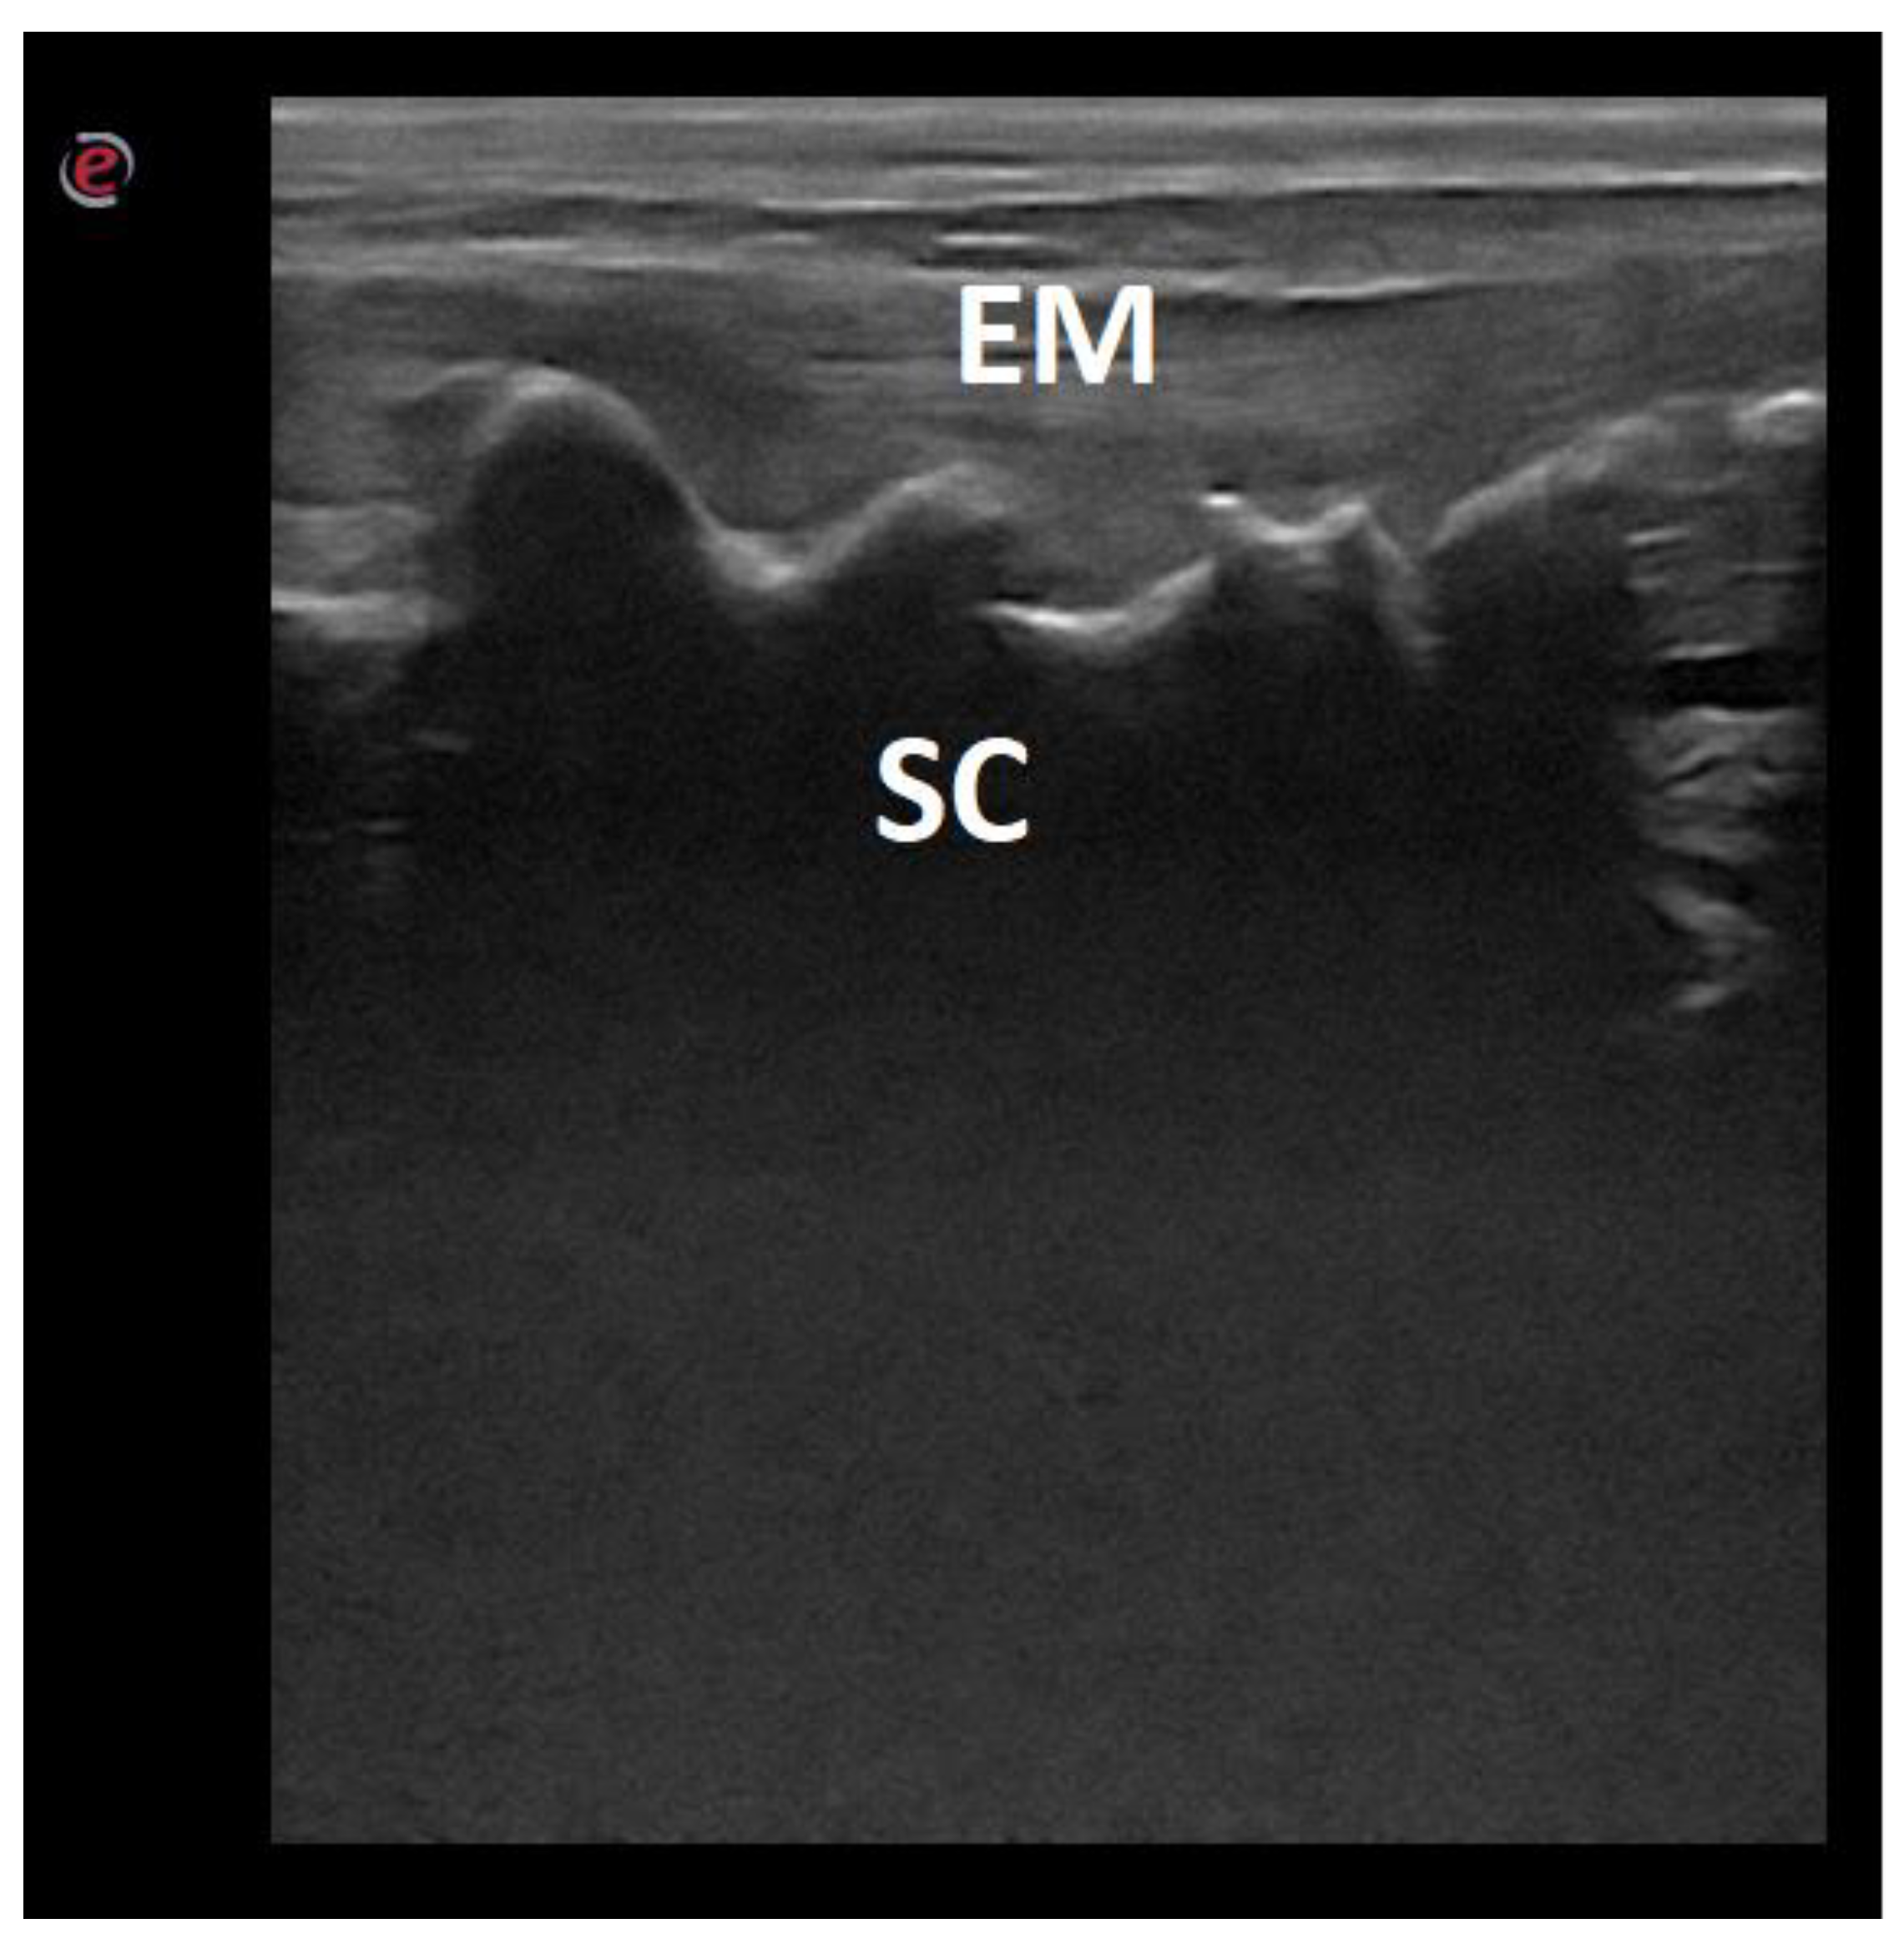

- Lopes, É.R.; Bellegard, G.M.; Cury, F.S.; Abreu, F.A.; Ambrósio, C.E.; Carregaro, A.B.; Hage, M.C.F. Evaluation of the applicability of musculoskeletal ultrasonography of the thoracolumbar and lumbar spine segment of healthy dogs. Pesqui. Veterinária Bras. 2018, 38, 2278–2283. [Google Scholar] [CrossRef]

| Vertebral canal floor | 11/47.83 |

| Intervertebral discs | 23/100 |